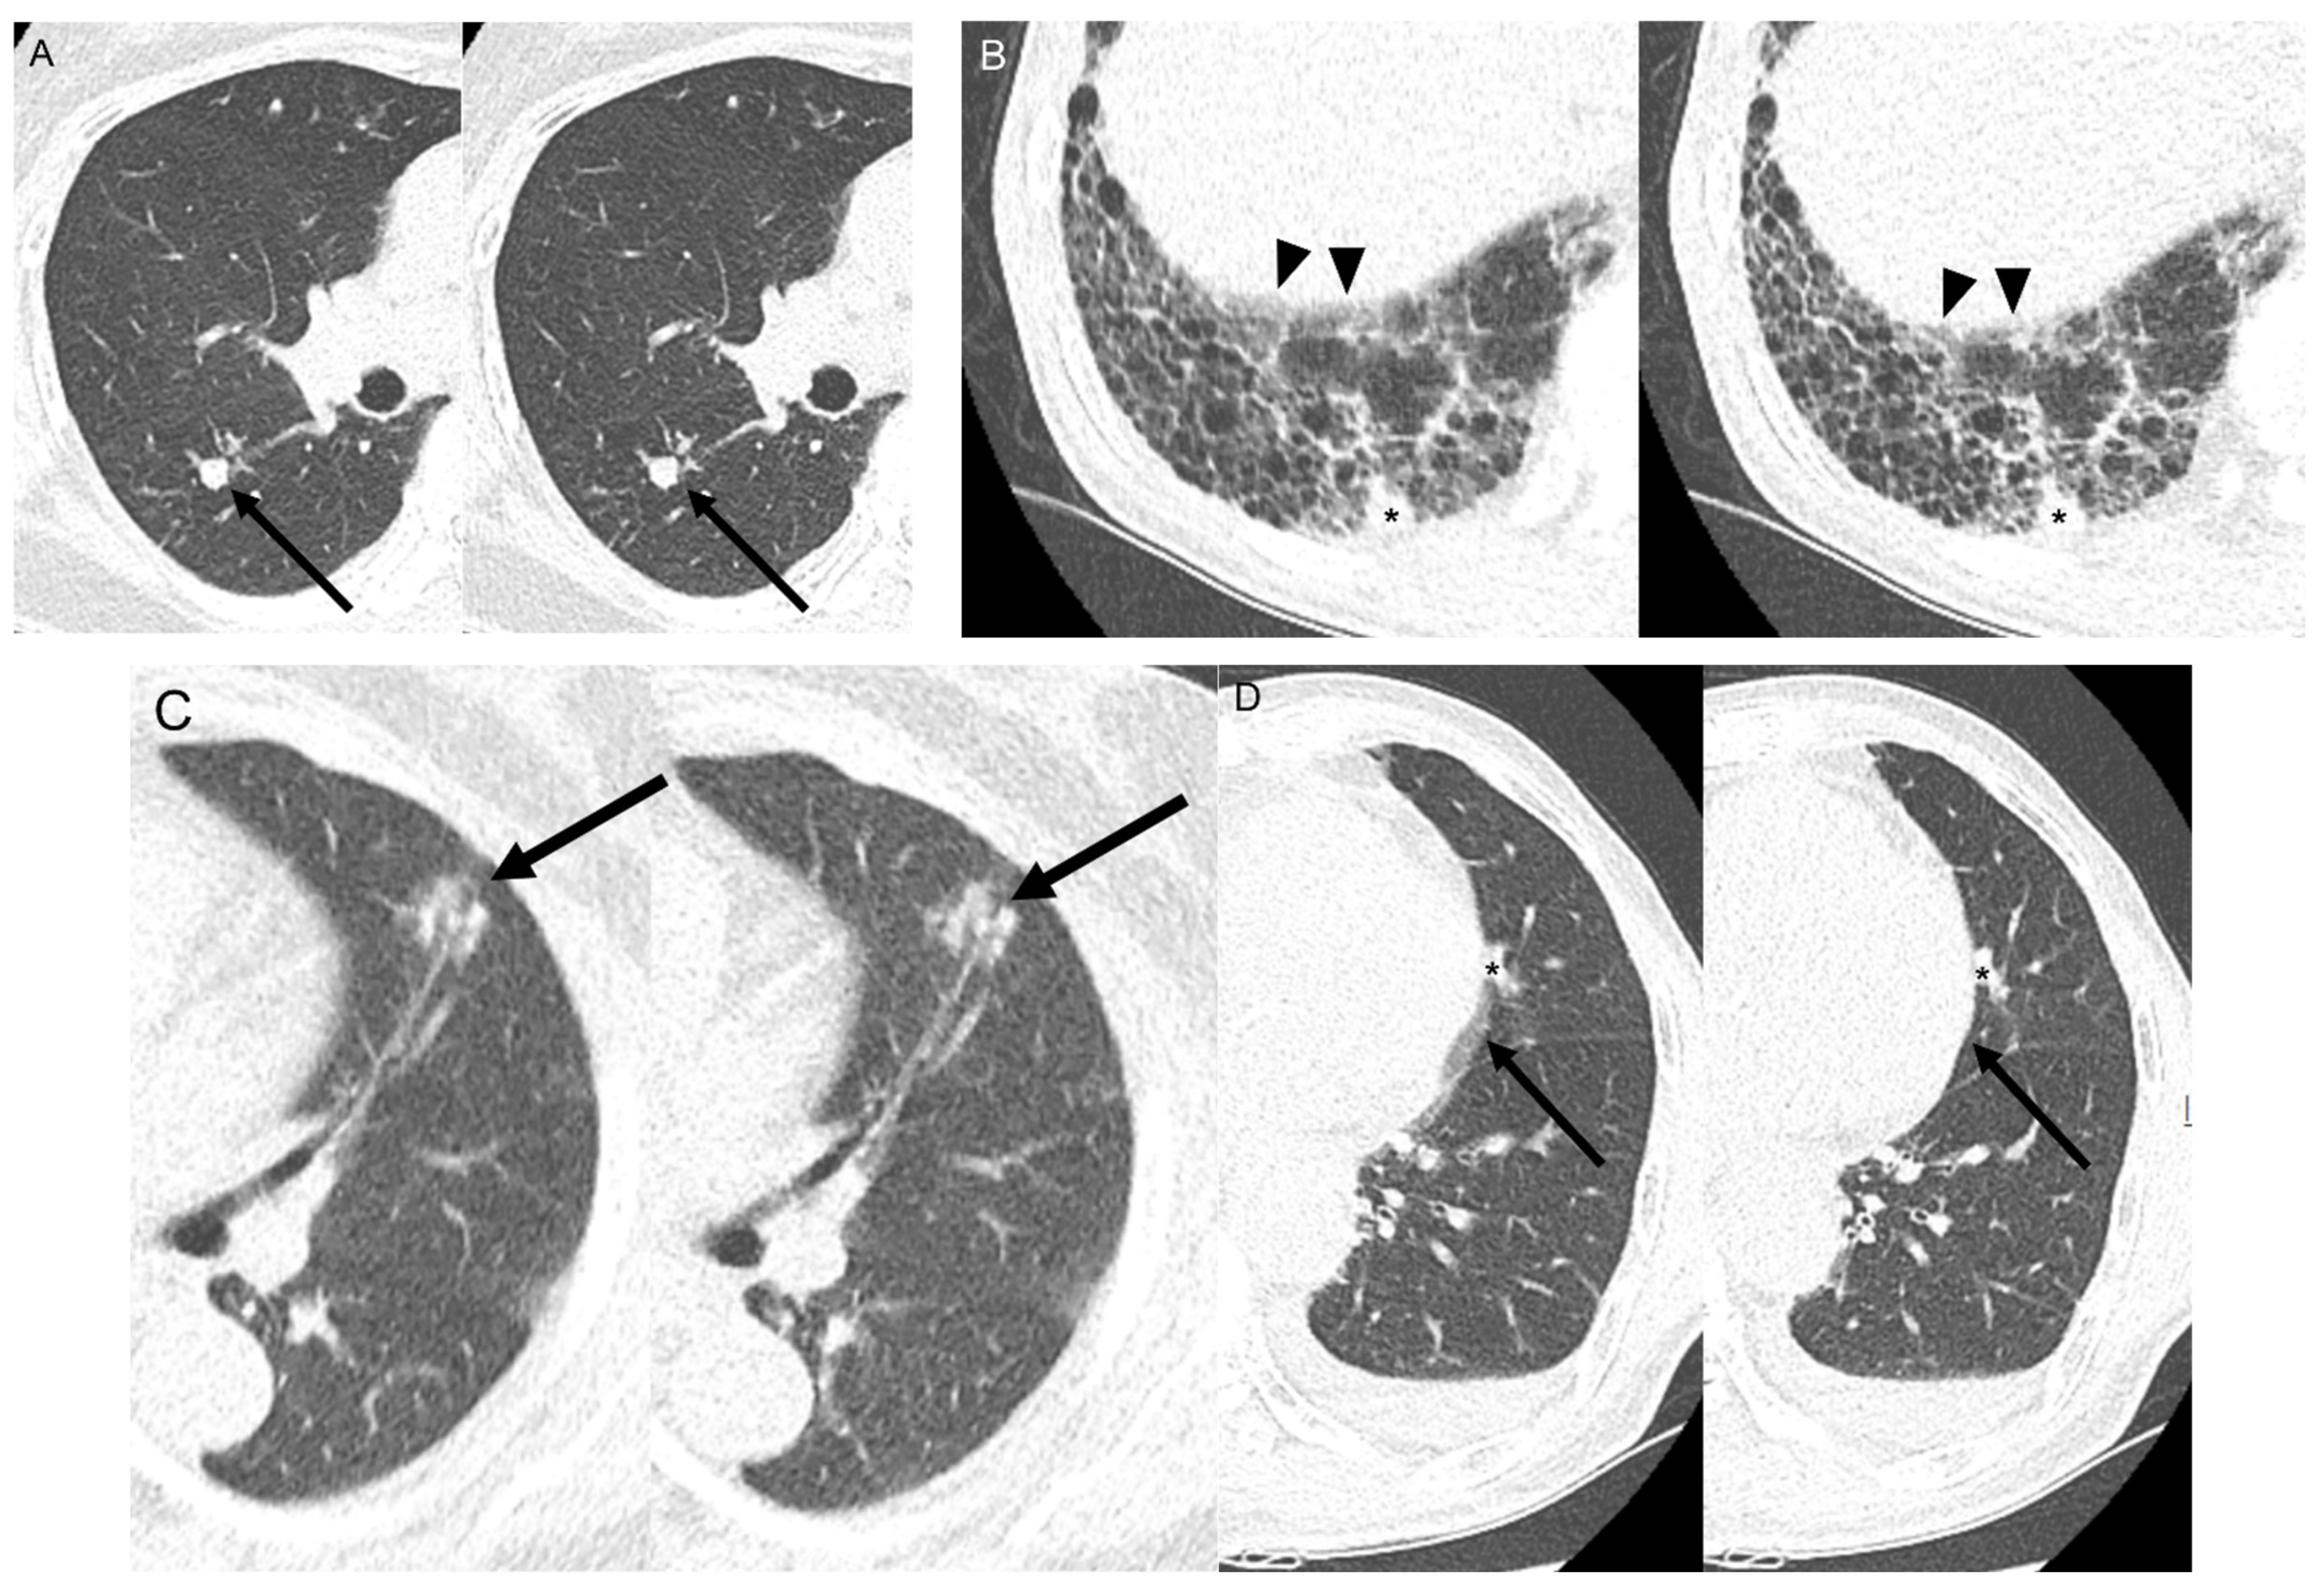

3.2. Objective Image Quality between SSSP and HSHP

3.3. Volumetry According to Nodule Classification

3.4. Subjective Image Quality Analysis between SSSP and HSHP

4. Discussion